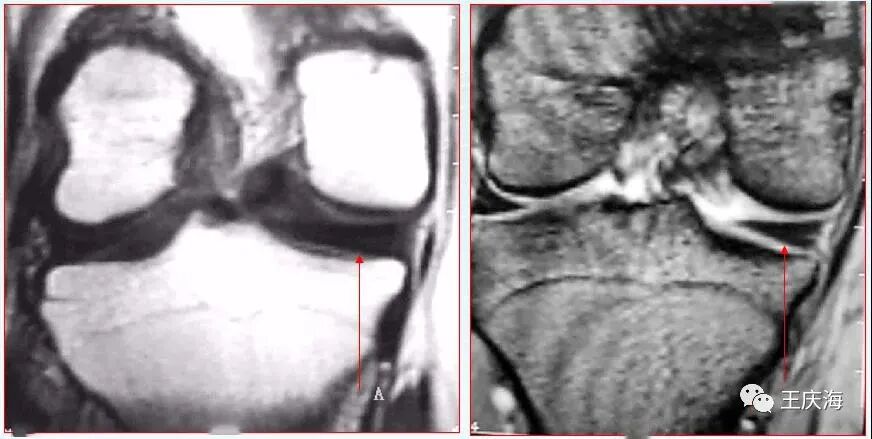

冠状面(图A)见外侧半月板体部宽度增宽,横断面(图B)示外侧半月板环较小。

大盘状半月板覆盖75%以上的一侧胫骨平台

矢状面T2WI(上图)显示半月板覆盖整个一侧胫骨平台,形态不规则,信号不均匀。

厚板型盘状半月板,矢状面T1WI(图A)和T2WI(图B)显示半月板前后角连续。冠状面(图C)见半月板体部的横向宽度明显增大,等同于外侧胫骨关节面的横径,半月板游离缘厚度基本与囊缘一致。

楔型盘状半月板,冠状面T1WI测量半月板体部的横向宽度超过外侧胫骨平台关节面宽度一半以上,半月板游离缘的厚度明显小于囊缘。

少见病例-内侧盘状半月板关节腔造影前(图A)后(图B)冠状面T1WI均呈现楔型盘状半月板,其体部宽度明显超过内侧平台关节面宽度的1/2以上。